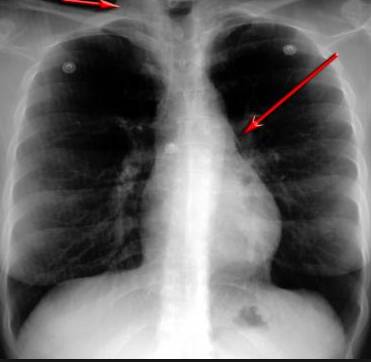

并且,因為呼吸系統結構復雜,在體檢時醫生很難通過一種檢測手段,判定早期患者的病情。

這臺4D掃描儀

能讓醫生有一雙可以透視的眼睛

把整個肺部看得清清楚楚!

4D的! 高清透視!

使用這臺掃描儀,將直接把器官變成3D圖形!細微的毛細血管,幾毫米大的肺泡和支氣管,都將能看的一清二楚!

你的每一個氣泡,每一段支氣管,哪兒有病變都清清楚楚的將展示在醫生面前!

也就是說在一切都還沒開始惡化前,把這些有問題的器官組織都暴露的一清二楚:

沒有這項新技術,醫生在做體檢的時候,很難通過一種測試斷定一個人是否有呼吸系統疾病。

可是現在他們不但能看到整個肺部的3維結構圖。還能看到空氣進入人體后的所有微小變動!